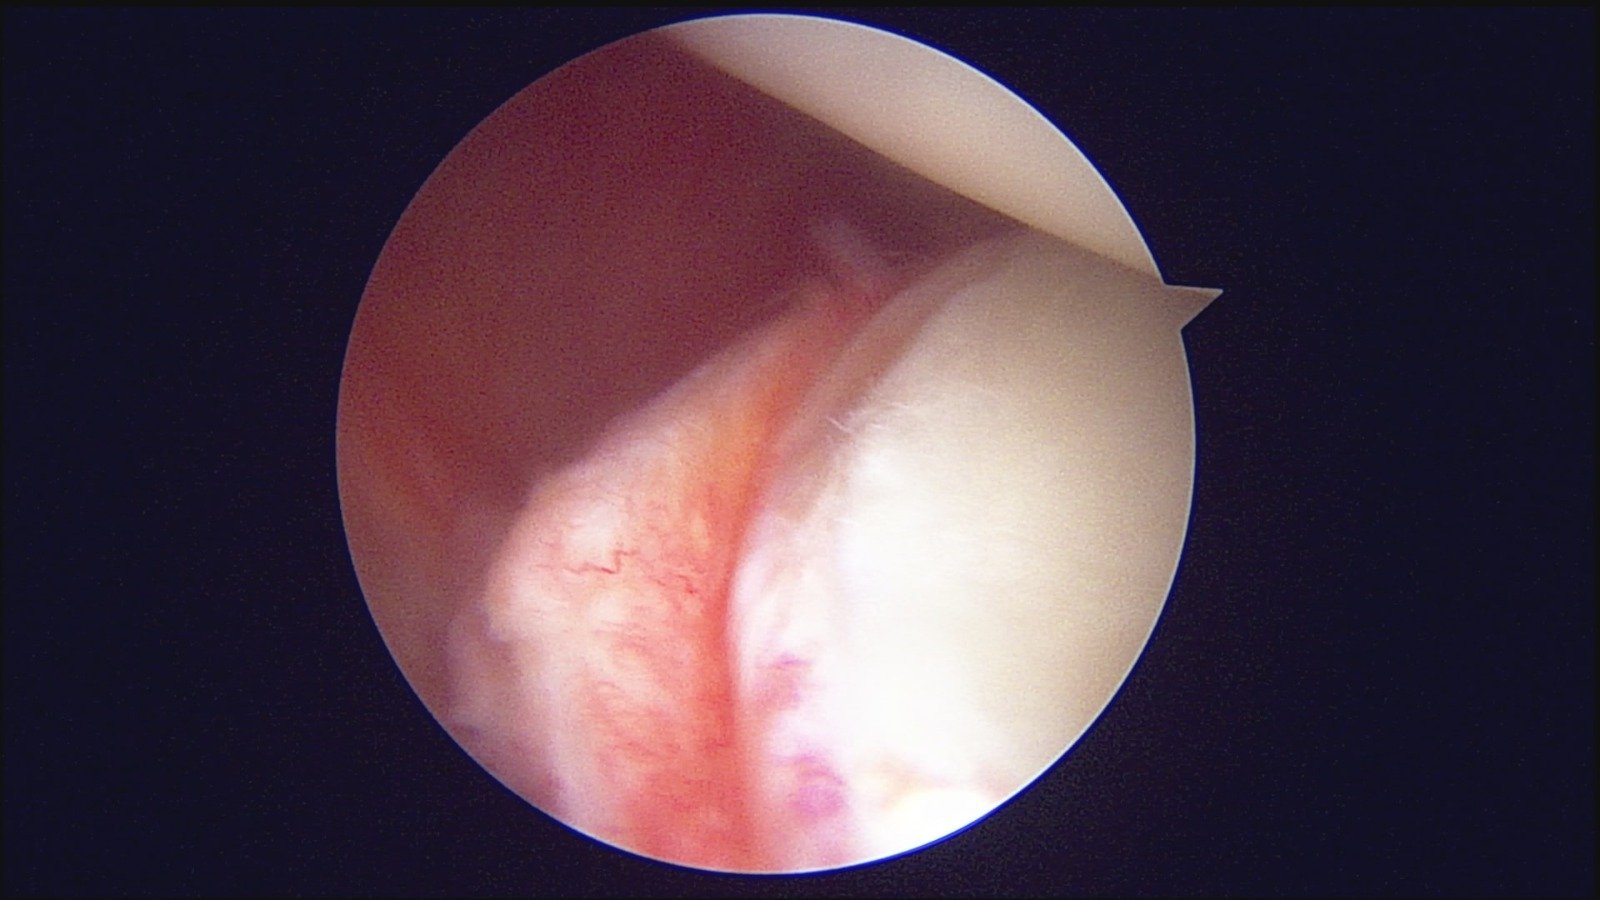

GalleryShoulder rotator cuff repair Meniscus root repair Meniscus repair Bankart repair for recurrent shoulder dislocation ACL reconstruction Machines Instruments